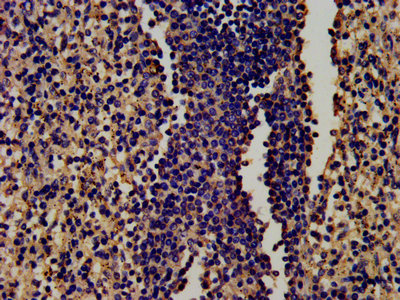

IHC image of CSB-PA00870E0Rb diluted at 1:450 and staining in paraffin-embedded human spleen tissue performed on a Leica BondTM system. After dewaxing and hydration, antigen retrieval was mediated by high pressure in a citrate buffer (pH 6.0). Section was blocked with 10% normal goat serum 30min at RT. Then primary antibody (1% BSA) was incubated at 4°C overnight. The primary is detected by a biotinylated secondary antibody and visualized using an HRP conjugated SP system.